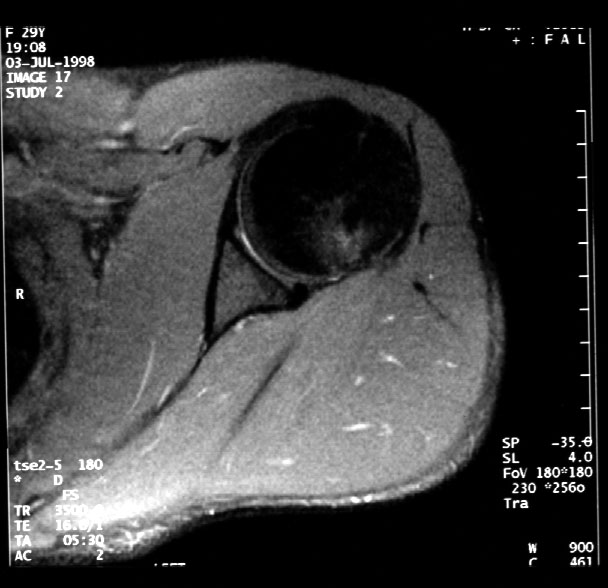

Normal MR Left Shoulder (axial) -- Identify: humeral head, glenoid, glenoid

labrum, deltoid,muscle, subscapularis muscle, subscapularis tendon